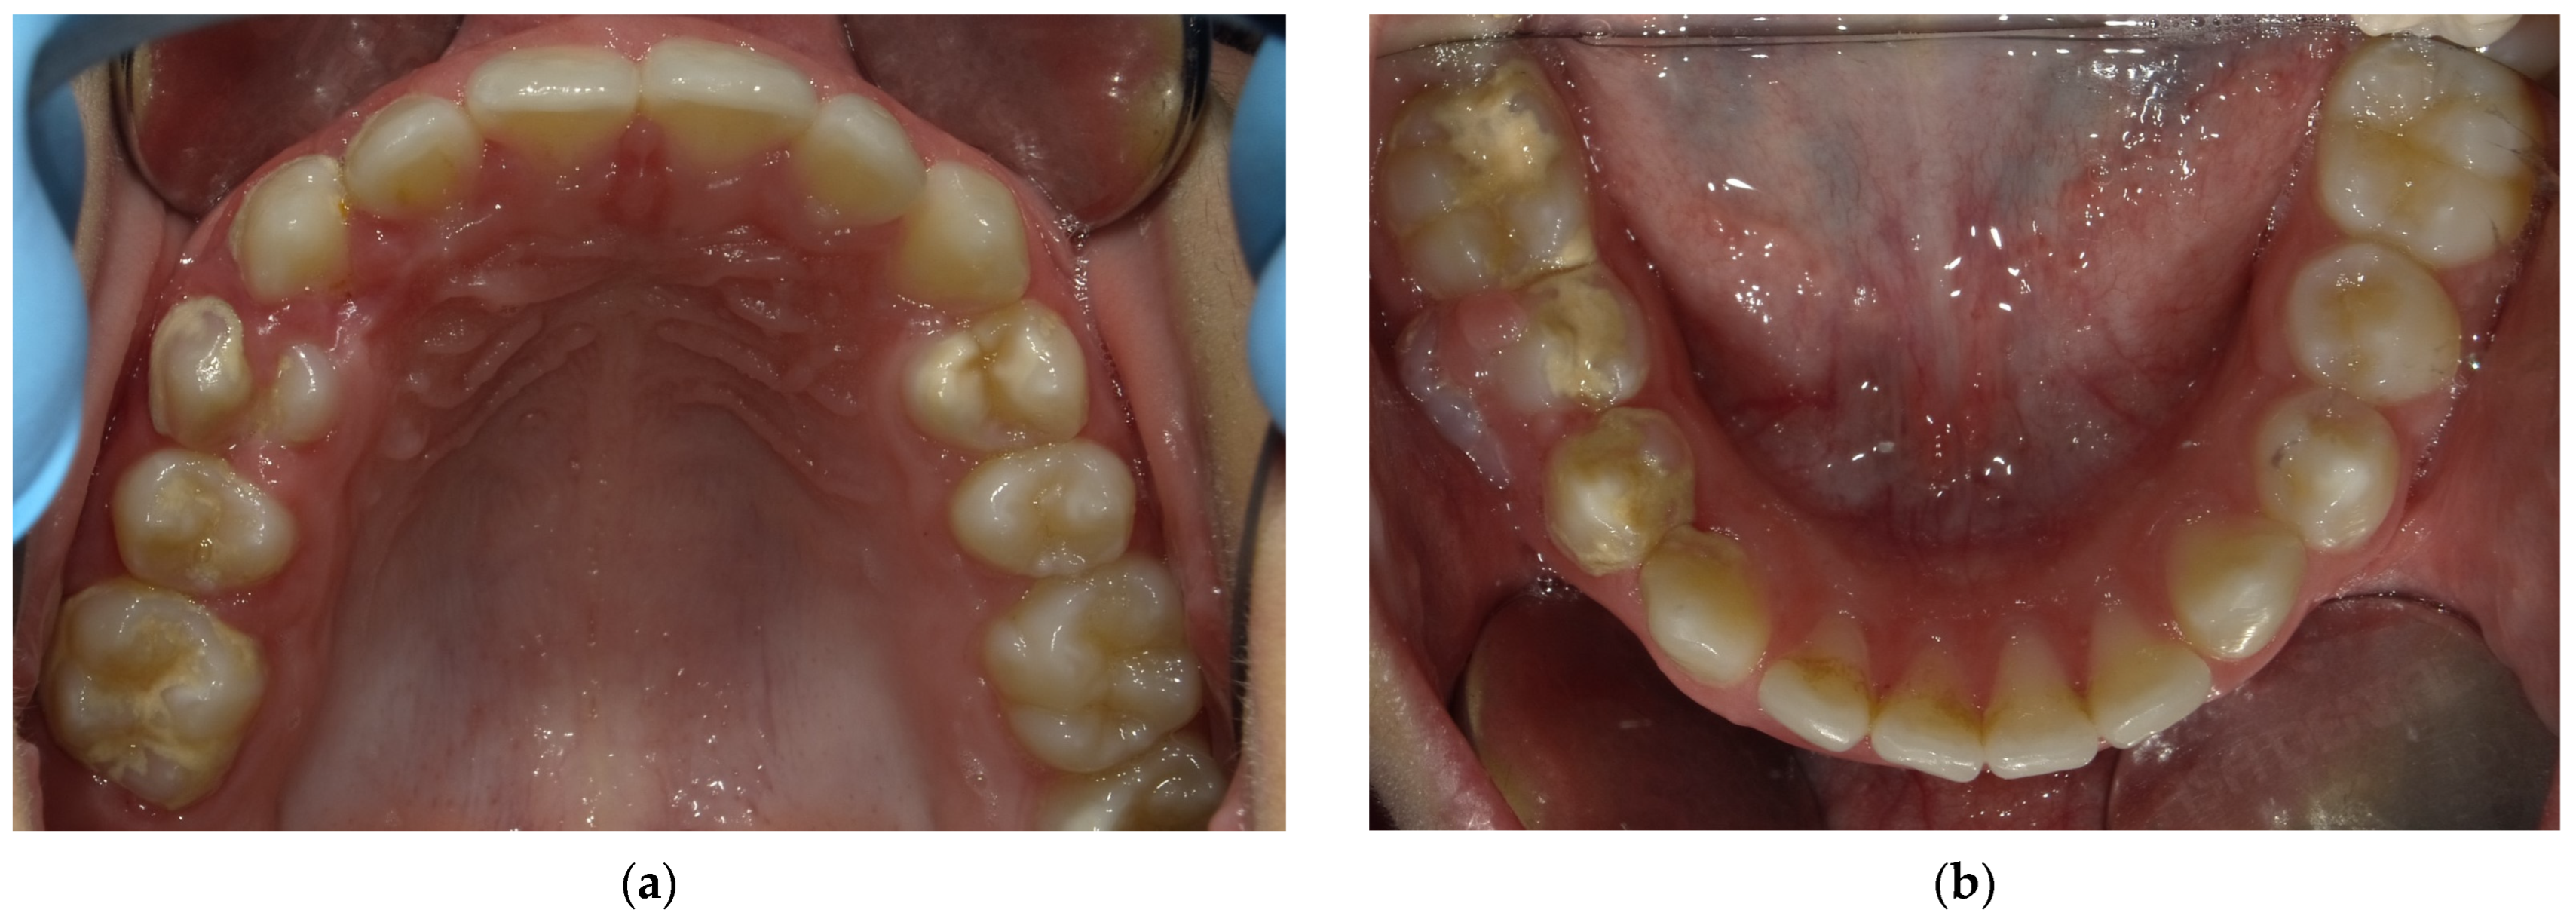

2.2. Clinical Findings

2.3. Diagnostic Assessment